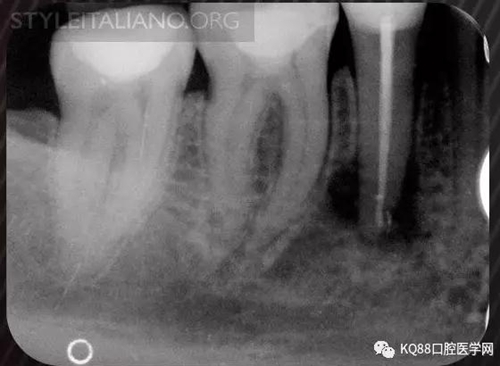

Img. 3 - The frequency of post-endodontic pain is higher in teeth with periapical or periradicular lesions. Infected debris can be forced in the periradicular tissue through a resorpted apex, thus generating acute inflammation. Creating a glide path prior to instrumentation and using a step-down technique can reduce the amount of extruded debris.